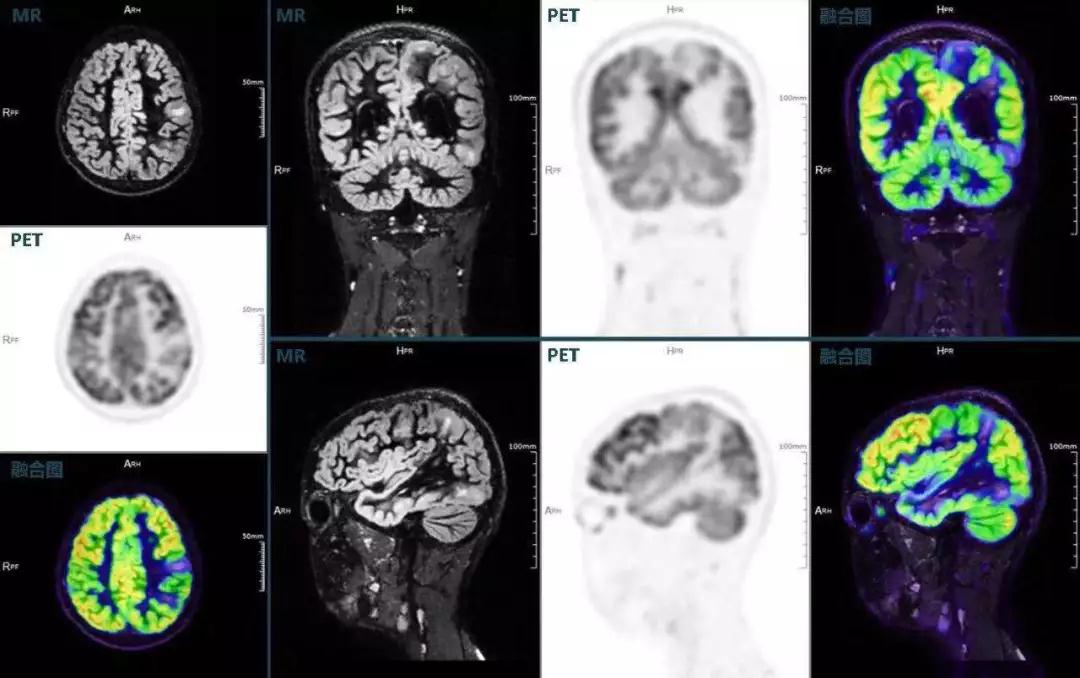

癲癇

不僅如此,聯(lián)影“時空一體”超清TOF PET/MR還搭載了大量可用于神經疾病領域的高級應用,如DIR(Double Inversion Recovery雙反轉恢復)序列能夠清晰顯示大腦皮層的結構成像,對于皮層腫脹,膠質增生等癲癇的影像征象都能清楚呈現;DTI(Diffusion Tensor Imaging彌散張量成像)高級應用能夠顯示細小的神經纖維束缺損,以更加定量的形式為醫(yī)生提供一個全新的診斷維度,輔助醫(yī)生精準診斷。

(結節(jié)性硬化,MR DIR序列清晰顯示腦皮層病理改變,PET顯示了病灶區(qū)域FDG的低濃聚。PET/MR融合顯像同時提供了結構異常改變和功能變化的信息。)